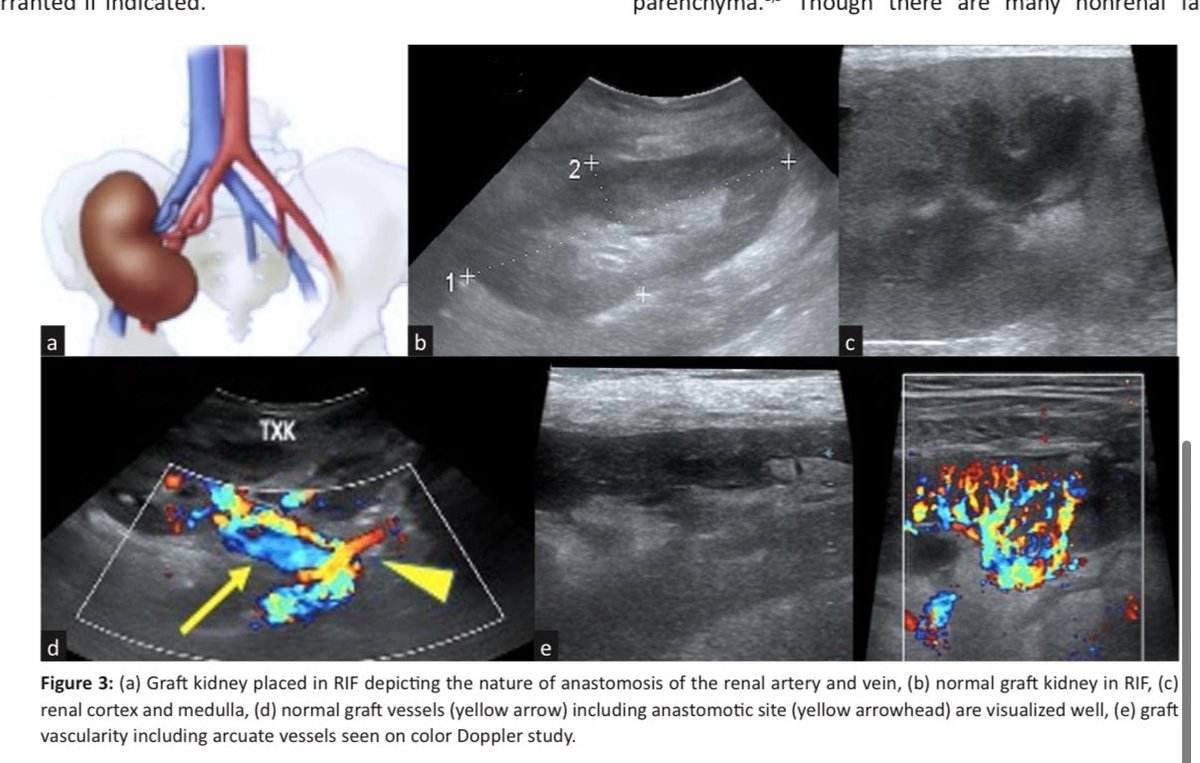

🫘POCUS in Renal Transplant indianjnephrol.org/utility-of-poc… Nice review in Indian Journal of Nephrology